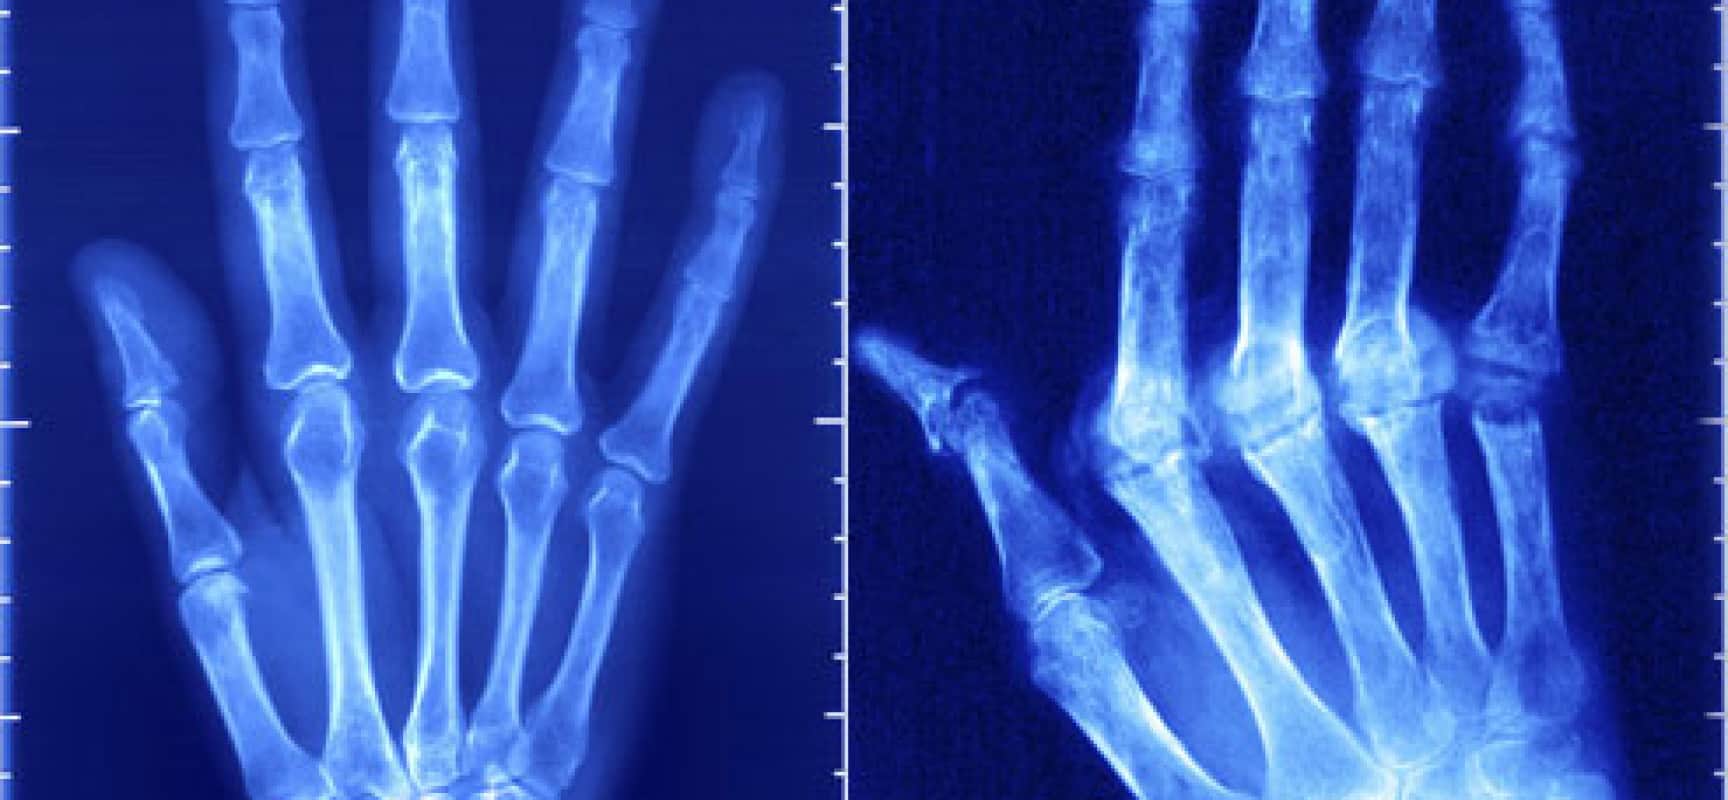

إلتهاب المفاصل الرثوى قد يمتد ليصل إلى الجلد والرئتين وقد يمتد إلى العمود الفقرى ومفاصل الورك، كما أن الإصابة قد تتركز فى كل من مفاصل اليدين والقدمين ، كما أنه يسبب تشوه وإعاقة بالجزء المصاب من مفاصل الجسم مما يؤدى إلى حدوث ضعف بالحركة وعدم القدرة على تحريك مفاصل الجسم، فقد يؤدى إلى حدوث الشلل أو حدوث إنعدام الإنتاجية، أو حدوث أوجاع أو تورم بالجزء المصاب بالجسم.

• حدوث تشوه فى شكل المفاصل.

• حدوث تورم فى كل من اليدين والقدمين.